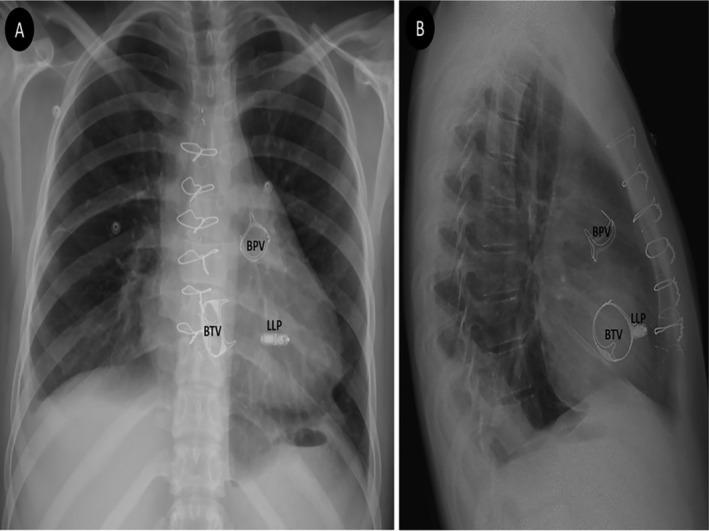

A 21-year-old man, known case of the repaired congenital heart disease, developed complete atrioventricular block (AVB) one week after simultaneous bioprosthetic pulmonary and tricuspid valve replacement and atrial septal defect repair. Considering the persistence of the AVB, it was decided to implant a permanent pacemaker. After considering all available options and the issues related to the patient, it was decided to implant a leadless pacemaker (LLP). A Micra pacemaker was implanted successfully, and the patient was discharged in good condition and without any complications. Follow-up evaluation showed appropriate LLP and bioprosthetic valve functioning. Limited prior experiences and the present report showed that LLP appears to be an ideal option in the patients with bioprosthetic tricuspid valve complicated by conduction disorders.

一名21岁男性,为先天性心脏病修复术后患者,在同期进行生物瓣肺动脉瓣和三尖瓣置换及房间隔缺损修复术后一周出现完全性房室传导阻滞(AVB)。考虑到房室传导阻滞持续存在,决定植入永久性起搏器。在考虑了所有可用选项及与患者相关的问题后,决定植入无导线起搏器(LLP)。成功植入了美敦力Micra无导线起搏器,患者出院时情况良好,无任何并发症。随访评估显示无导线起搏器及生物瓣功能正常。既往有限的经验及本报告表明,对于合并传导障碍的生物瓣三尖瓣患者,无导线起搏器似乎是一个理想的选择。